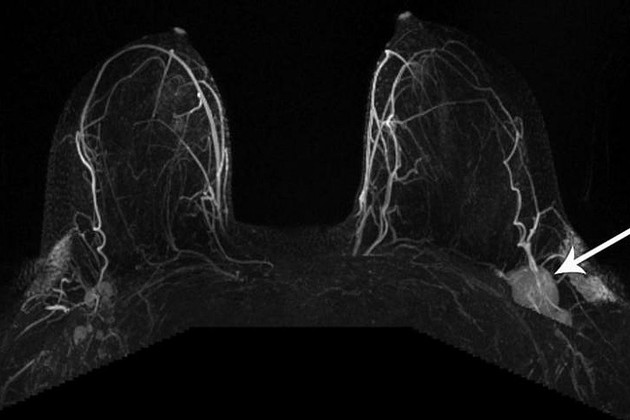

Esta mamografía, tomada después de que una paciente recibió la vacuna contra el covid-19, muestra un ganglio linfático inflamado. Situaciones similares habían estado sucediendo en los centros de mamografías de todo el país. A medida que los radiólogos compararon notas con sus colegas, se empezó a correr la voz. «Todos empezamos a hablar de ello, y fue como un incendio forestal», dijo la Dra. Connie Lehman, jefa de Imágenes Mamarias en el Departamento de Radiología del Massachusetts General Hospital. «No puedo decirte cuántas mujeres muestran nódulos en las mamografías y muchos pensaron que no sería tan común», dijo Lehman, quien también es profesora de Radiología en la Escuela de Medicina de Harvard.